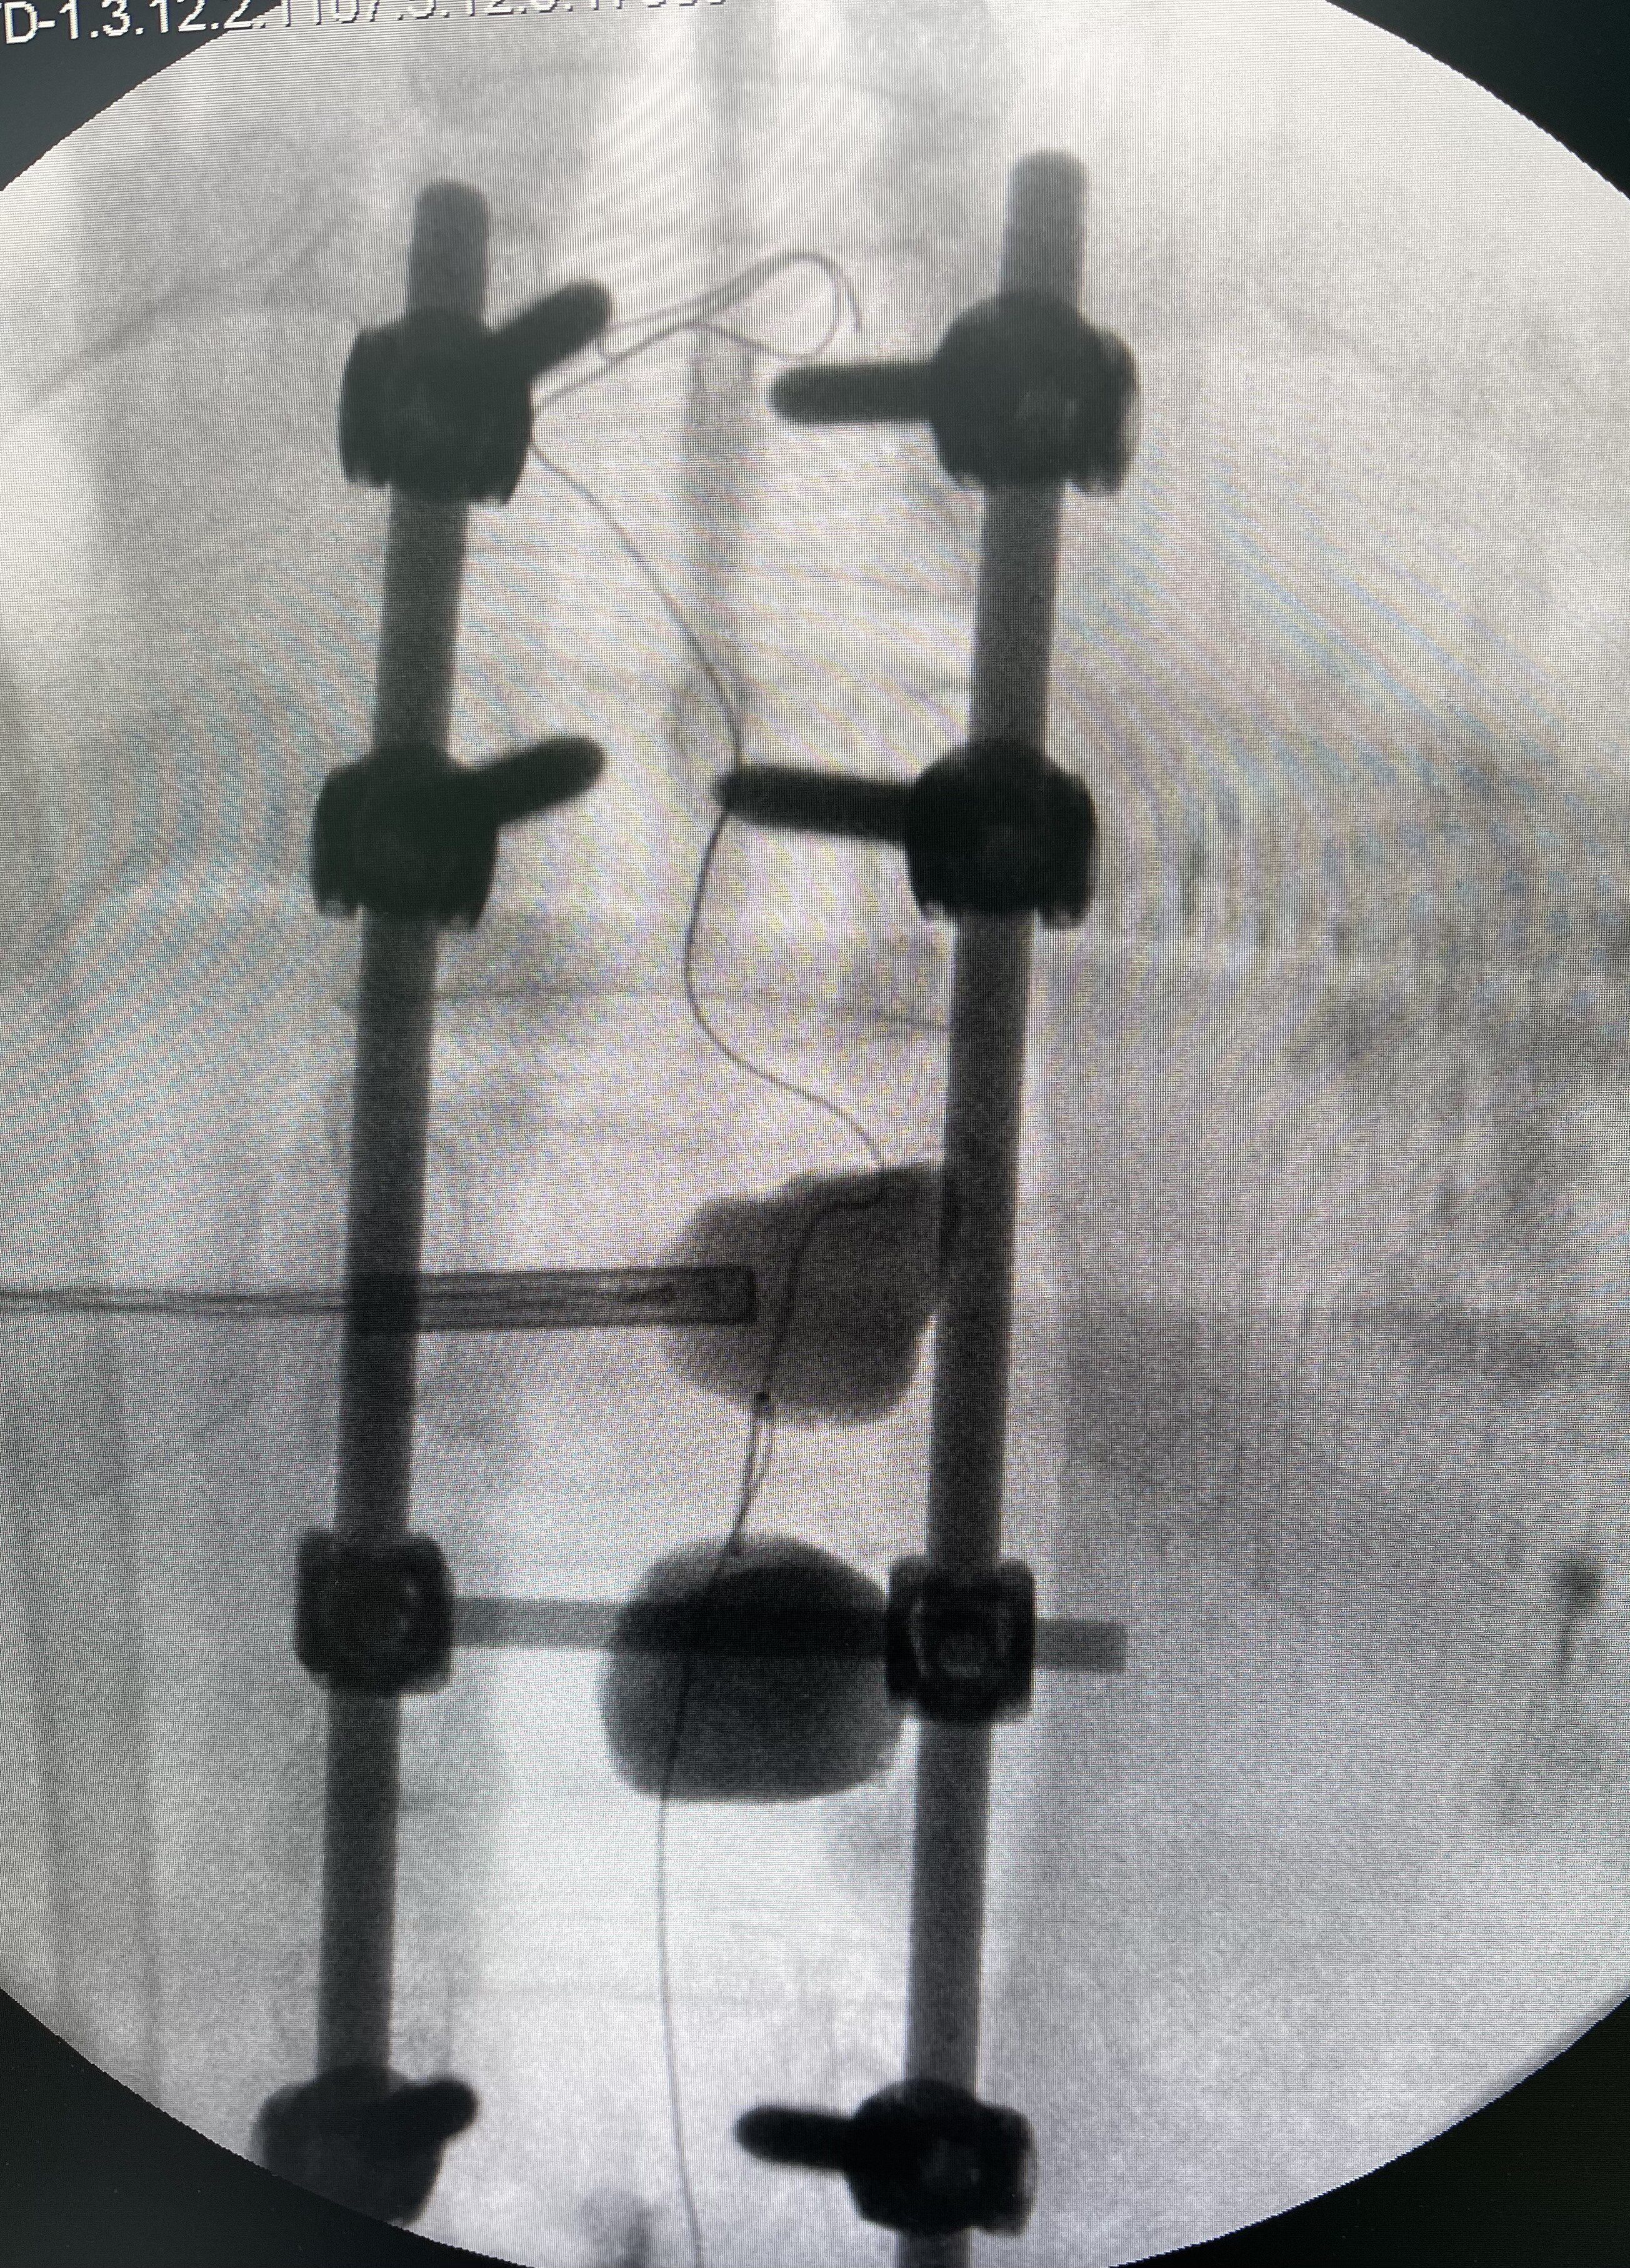

4.神经受压症状 最常见的脊柱转移瘤在骨破坏的同时,局部软组织肿块形成压迫脊髓或神经根;以及椎体的病理性骨折瘤骨突入椎管和神经根管,出现脊髓和神经根受压症状,严重时出现瘫痪(下肢无力、麻木,大小便障碍等)症状!

出现这几种常见的情形后,一、做好及时就医,前往专科就诊。二、相信骨转移仍然可治(a.药物治疗:骨保护药物;b.放射治疗:止痛、抗肿瘤;c手术干预:经皮穿刺椎体球囊扩张成形术、骨成形术等微创手术,病理性骨折开放手术,脊柱转移瘤的分离手术?立体定向放疗技术结合等)。三、相信合理的规范治疗,骨转移瘤仍然可以达到带瘤生存,部分单发转移积极治疗后,甚至可达到无瘤生存。四、由此,保持良好的心态,积极阳光的接受治疗同样对康复很关键。